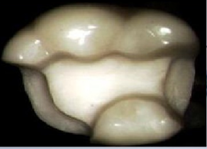

嵌體根據覆蓋牙面的不同,可以分為單面嵌體、雙面嵌體和多面嵌體,如圖所示:

(1)單面嵌體

(2)雙面嵌體

(3)多面嵌體